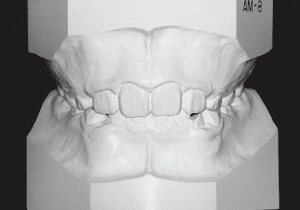

2 After Phase 2 Treatment 6-6-’94

The first phase of treatment involved extracting the left and right maxillary deciduous canines. The space created was used to forcibly retract the four anterior teeth, thereby aiming to improve lip closure function (6–9, 11). Morphological changes suggest that lip function differed before and after treatment (6, 9). Subsequently, the first premolars erupted, but extraction is planned to secure space for canine eruption (10). A Class II molar relationship remains, but the significant overjet has improved (11).

In the maxilla, insufficient space for canine eruption was inevitable, necessitating extraction as part of the treatment plan. The maxillary first premolars on both sides were extracted during routine observation to create space for canine eruption (14). Eventually, the canines erupted and settled into relatively favorable positions (15,19,20). In the mandibular dentition, crowding was also present, leading to extraction of the mandibular first premolars on both sides. Treatment with full bracket was then initiated (17).